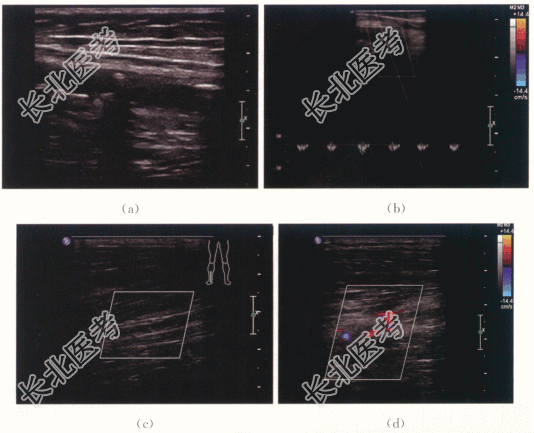

患者,男,67岁,因“5年前无明显诱因出现双下肢发凉怕冷”就诊,双足明显,未予重视。2年前步行时双下肢乏力,右侧明显,仍未系统治疗。半年前无诱因双足发凉怕冷明显加重,以右侧明显,步行约30~50m便被迫停止。

患者神清,气平。BP150mmHg/90mmHg。未见颈静脉怒张。双侧足背动脉搏动减弱。

TG2.9mmol/L,TC10.6mmol/L,HDL0.7mmol/L,LDL2.4mmol/L。

二、影像资料及诊断

下肢动脉硬化性闭塞症。